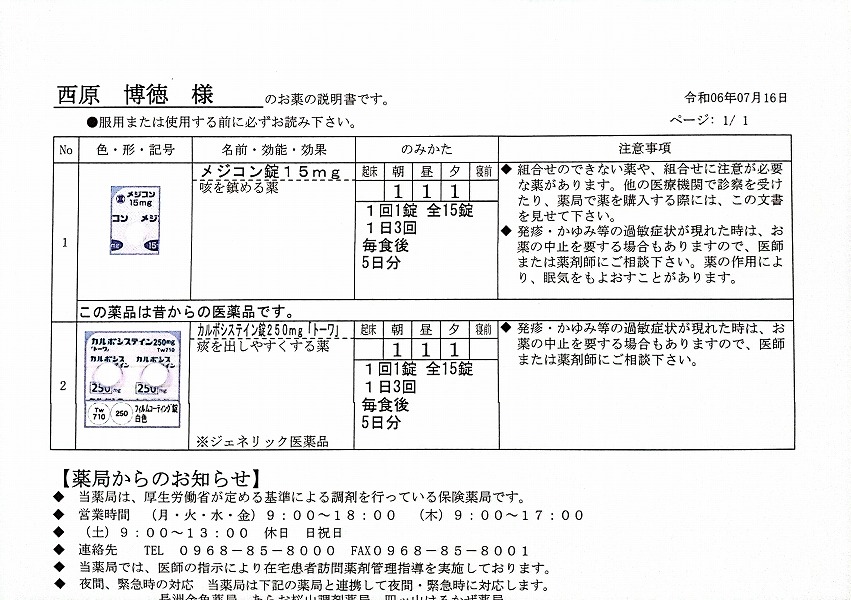

2024.7.12(金) 2回目のコロナ感染 7.16(火)検査で陽性

2023.11.13 ウイルス性の風邪と診断 熱の最大は13日夜 37.1℃